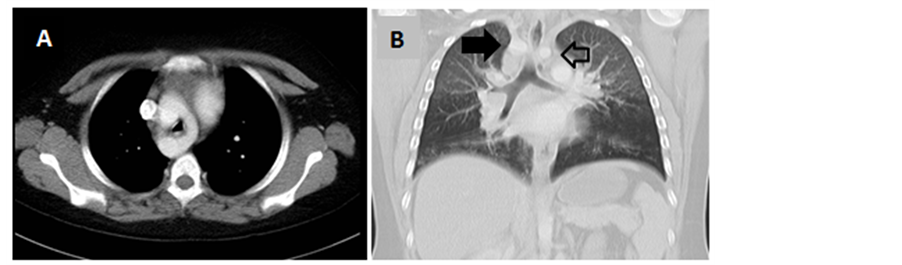

The chest CT and right cardiac catheterization revealed DAA surrounding the trachea and esophagus with right arch dominance and compression to trachea. No intracardiac defect was seen on both the CT and angiogram (Figure 2 and Figure 3). Besides DAA, chest CT results also revealed bronchiectasis. No compression of esophagus was seen in barium esophagogram. Spirometry test showed severe restrictive lung abnormalities, whereas sputum culture and antibiotic resistance test revealed Streptococcus viridans, which was sensitive to cefotaxime, cefazolin, erythromycin, and meropenem.

Figure 2. Chest computed tomography showed double aortic arch. Coronal view (A); Sagital view, right aortic arch (black arrow), left aotic arch (unfilled arrow) (B).